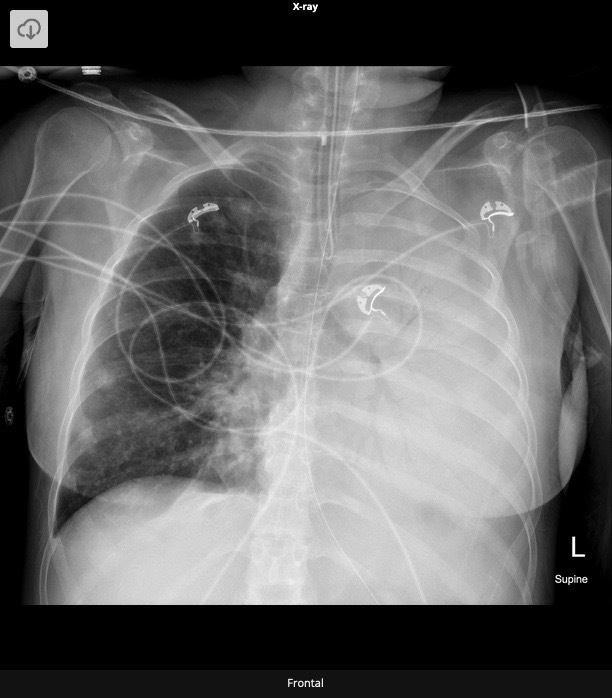

20.1 What is the abnormality in this CXR?

c. Pneumonia

Complete white-out of left lung with air bronchogram sign consistent with total consolidation. Patchy areas of ground glass opacities in right lung. There is silhouetting of the left heart border and left hemi-diaphragm. There is no rib crowding to suggest atelectasis.

Complete white-out of the hemithorax with air bronchograms and trachea in a central position is consistent with consolidation secondary to pneumonia. The patient is on linezolid, micafungin, and piperacillin-tazobactam pending culture and susceptibility studies.

Differential diagnosis of hemithorax white-out with a midline trachea include:

- consolidation

- pulmonary edema/ARDS

- pleural mass

- chest wall mass